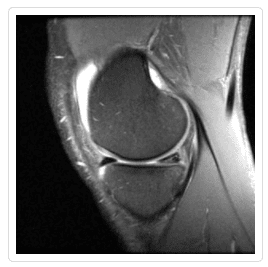

The second option, repair with stitches, can be performed under special circumstances. For tears in very young patients and tears that occur near the ends of the meniscus, where there is a better blood supply, Dr. Millstein may decide repairing the tear is a viable option. Although MRIs can give a good picture of what a tear looks like, the ultimate decision of whether to repair or cut out a meniscus tear will be made during surgery, when Dr. Millstein can best judge the vascularity of the tissue.A more detailed comparison of these two approaches can be found here.

Meniscus Tear Gallery